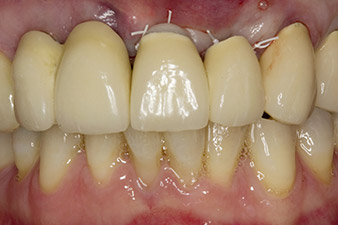

Lorsque le patient s'est présenté pour la première fois, les dents 21, 22 et 23 avaient été restaurées il y a 19 ans à présent, par des couronnes jumelées collées sur les implants en position 12/11 à l'aide d'une attache

(cf. Fig. 2).

Une fois la cicatrisation primaire obtenue, les tissus mous ont été formés à l'aide du bridge doublé à la base. Deux mois plus tard, la zone a été exposée au moyen d'une incision de la crête alvéolaire légèrement orientée côté palatin (Fig 2). Les dimensions de l'os alvéolaire se sont avérées suffisantes en position 22. Les Figures 2 et 4 illustrent la préparation du lit implantaire, le taraudage et la pose de l'implant à l'aide de l'Implantmed.